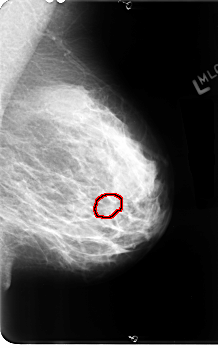

ics_version 1.0 filename B-3111-1 DATE_OF_STUDY 23 7 1996 PATIENT_AGE 44 FILM FILM_TYPE REGULAR DENSITY 3 DATE_DIGITIZED 22 1 1998 DIGITIZER LUMISYS LASER SEQUENCE LEFT_CC LINES 4888 PIXELS_PER_LINE 2856 BITS_PER_PIXEL 12 RESOLUTION 50 OVERLAY LEFT_MLO LINES 4864 PIXELS_PER_LINE 3040 BITS_PER_PIXEL 12 RESOLUTION 50 OVERLAY RIGHT_CC LINES 4792 PIXELS_PER_LINE 2880 BITS_PER_PIXEL 12 RESOLUTION 50 NON_OVERLAY RIGHT_MLO LINES 4824 PIXELS_PER_LINE 2960 BITS_PER_PIXEL 12 RESOLUTION 50 NON_OVERLAY |

FILE: B_3111_1.LEFT_MLO.OVERLAY TOTAL_ABNORMALITIES 1 ABNORMALITY 1 LESION_TYPE CALCIFICATION TYPE AMORPHOUS DISTRIBUTION CLUSTERED ASSESSMENT 4 SUBTLETY 3 PATHOLOGY BENIGN TOTAL_OUTLINES 1 BOUNDARY |